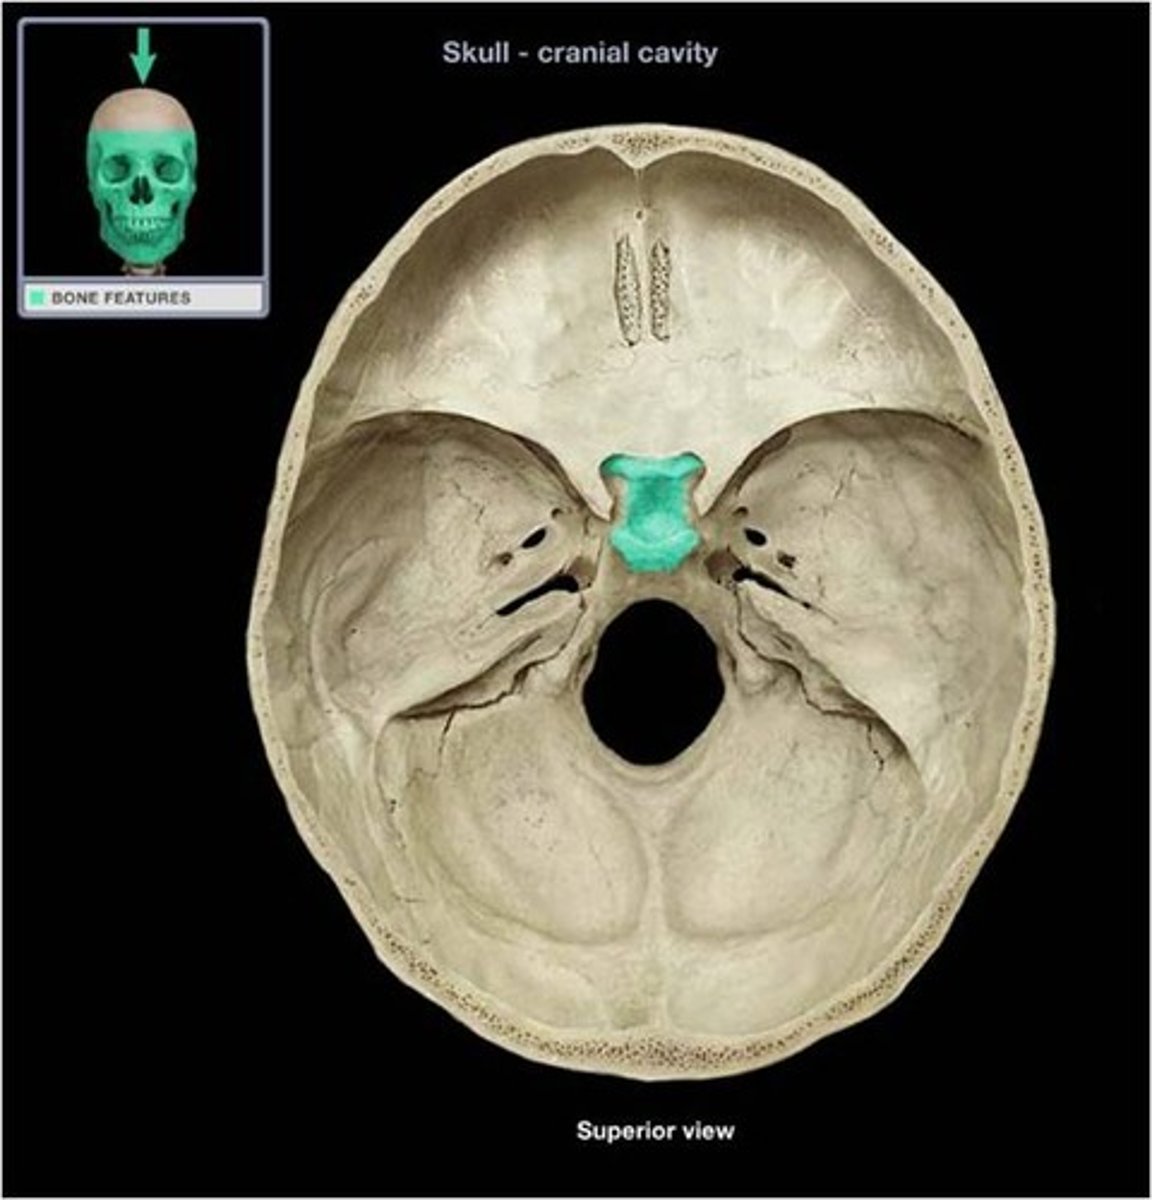

Sella turcica

Cristi Galli